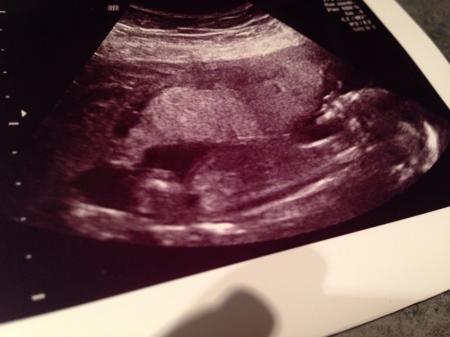

Hallo ihr lieben, ich bin zurück vom FA. Es ist alles ok, dem Böhnchen geht's gut. Ich hab eine Vorderwandplazenta und die Gebärmutter liegt schon recht hoch (Bauchnabel -2) Leider war der Ultraschall sehr kurz und er hat auch nicht sooo viel dazu gesagt:-( Irgendwie macht mir das sorgen, andererseits war es das letzte mal auch schon so. Er hat uns auch nicht das Herz gezeigt, ich glaube aber es gesehen zu haben!? Mein Sohn war aber trotzdem begeistern und hat auch ein Bild für seinen Geschwisterpass bekommen. Jetzt heißt es wieder 4!!!! Wochen warten:-( LG